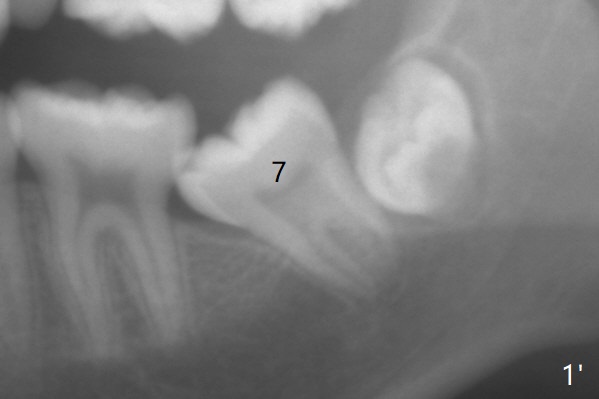

A 13.5-year-old man with crowding and L7s' mesial tilt (Fig.1).